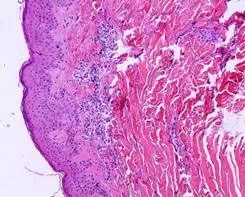

JD801系列真菌镜检、皮肤病理图文报告系统是江苏省捷达科技发展有限公司根据皮肤科真菌镜检和皮肤病理的需要研发的一套系列产品,具有数码图像(兼容模拟图像)采集、显示、处理(图像分割、图像和图形编辑等)、皮肤组织病理学细胞结构参数和光密度计量分析的功能。适用医院皮肤科及涉及医学图像分析的相关科室,医学院校和科研单位皮肤病理、形态学研究的科室。

●出具皮肤病理图文报告;